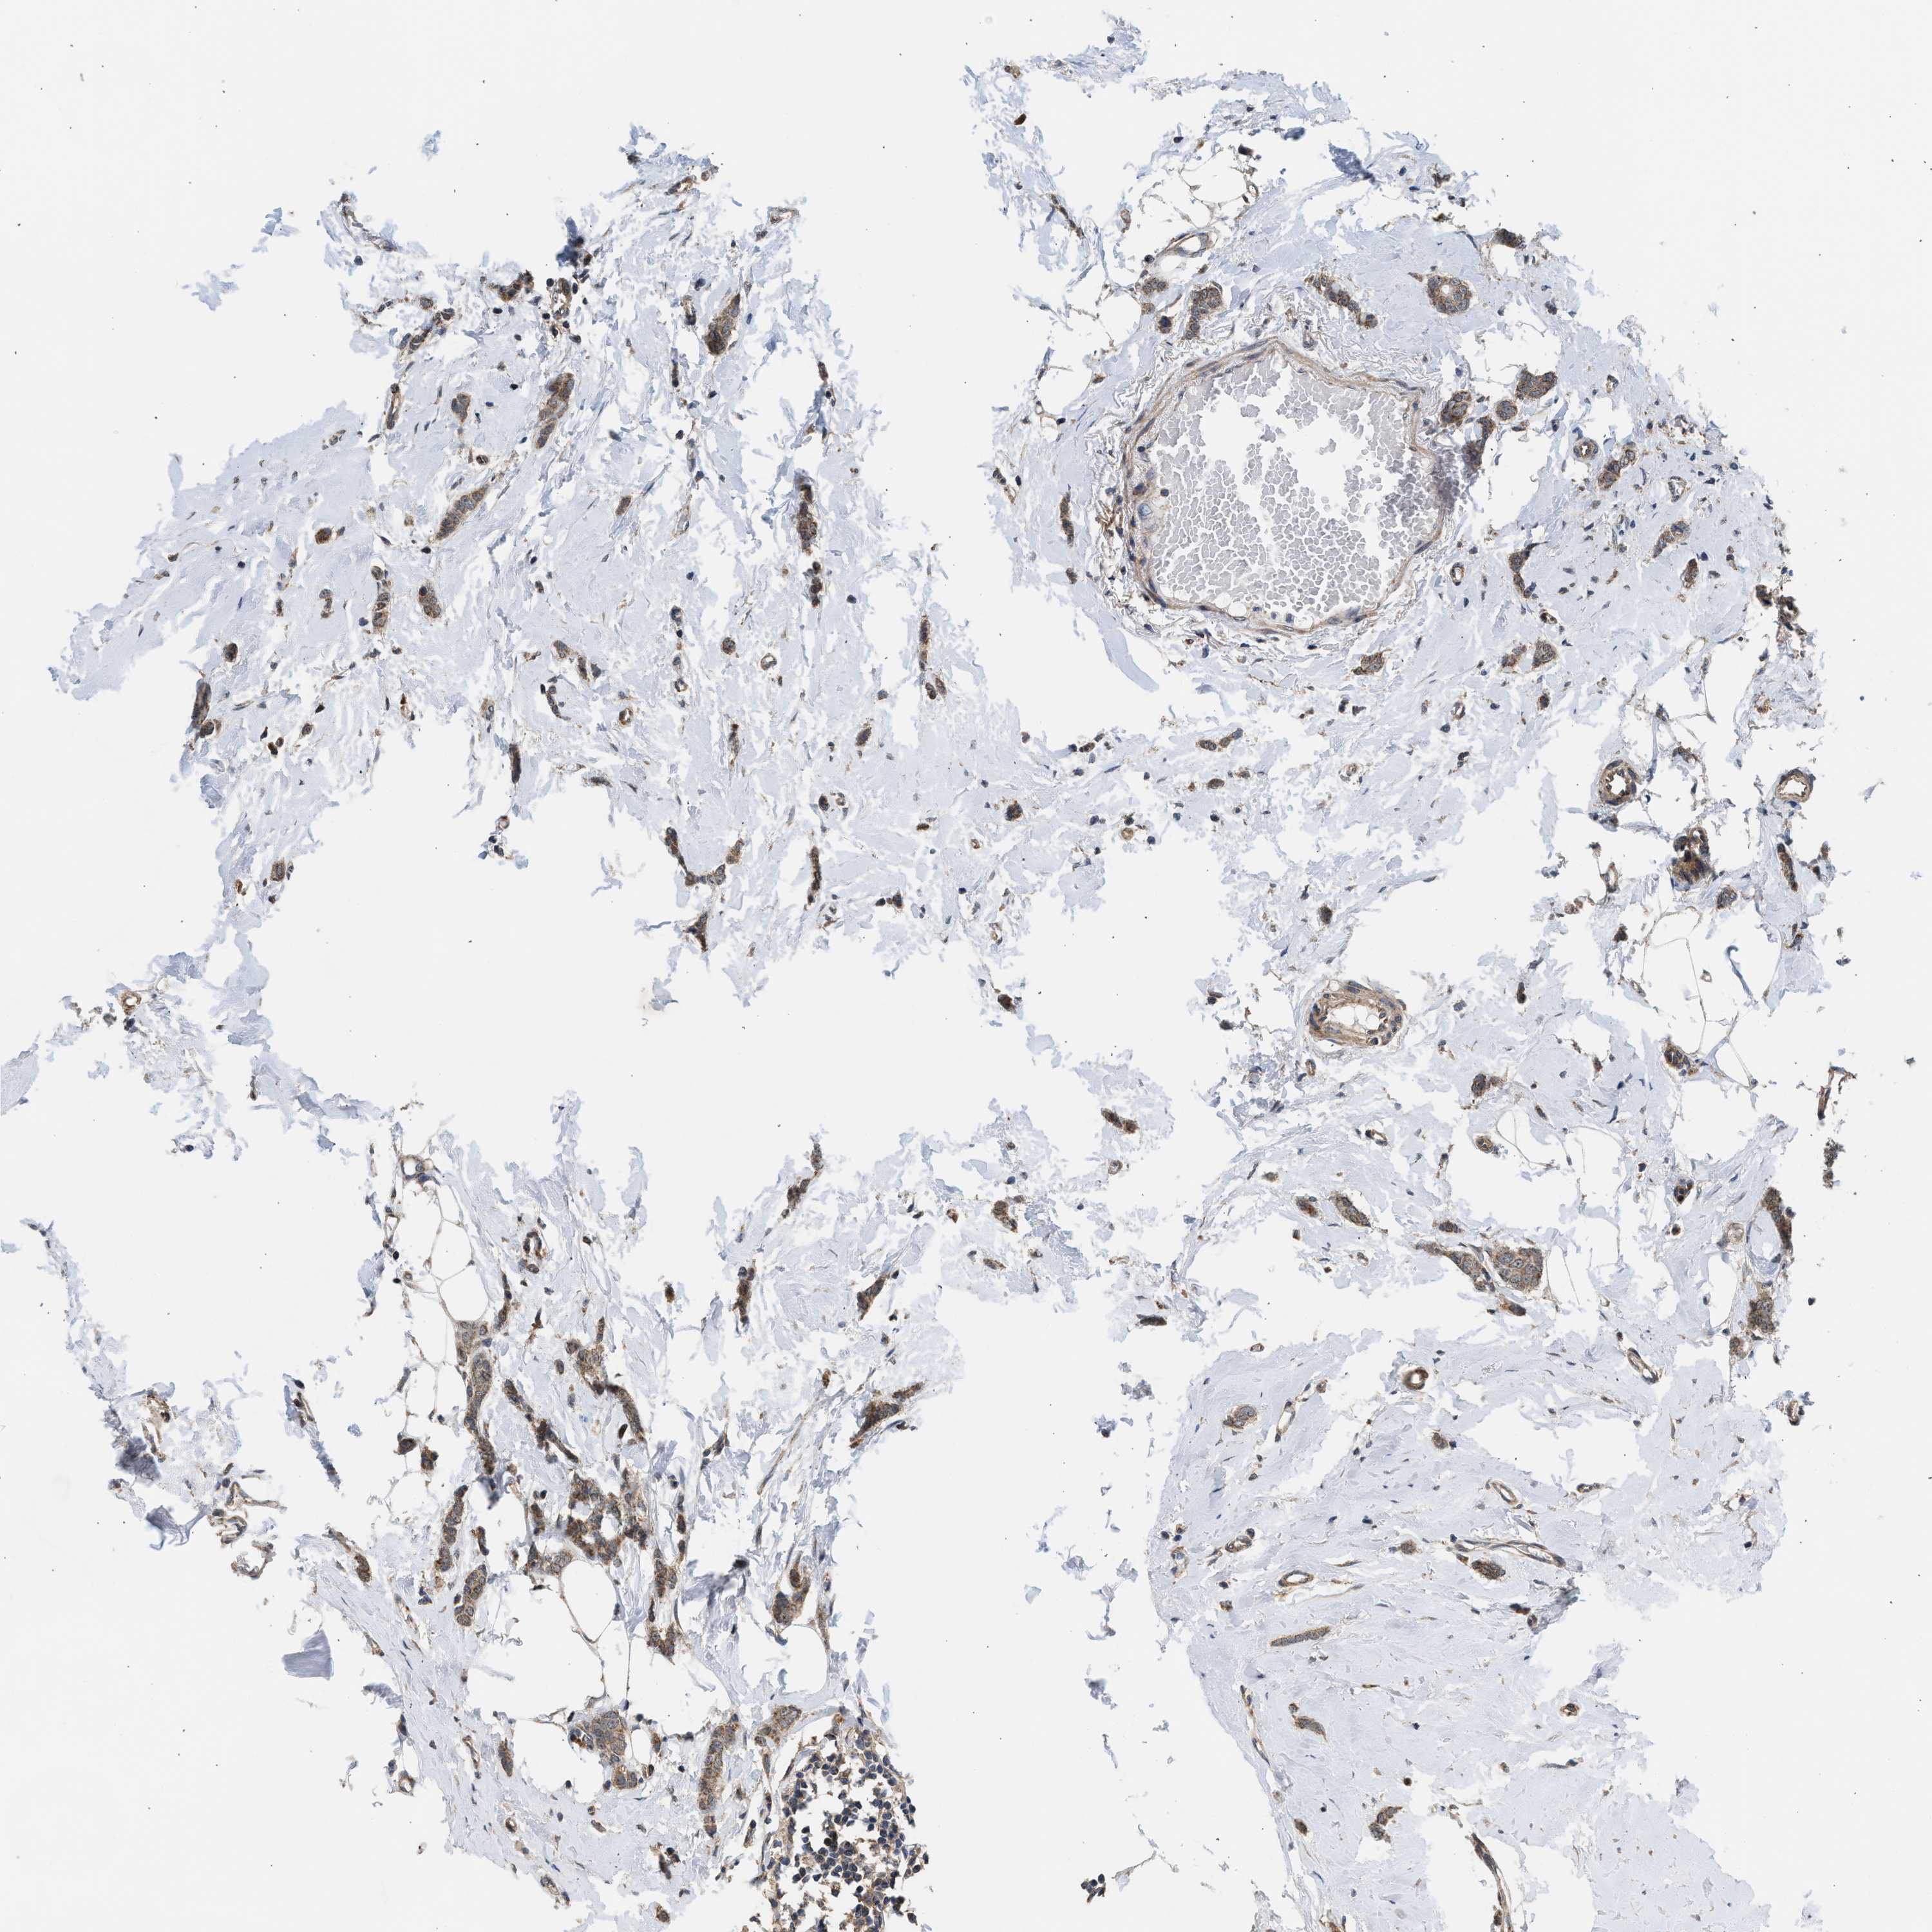

CANCER BREAST CANCER Show tissue menu

BRCA TCGA BRCA VALIDATION PROTEIN EXPRESSION

ANTIBODIES

AND

VALIDATION